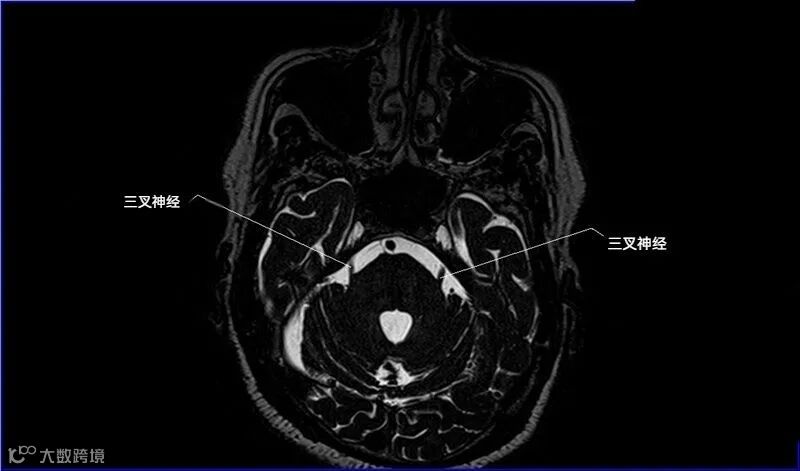

一嗅二视三动眼,四滑五叉六外展,

七面八听九舌咽,迷走及副舌下全。